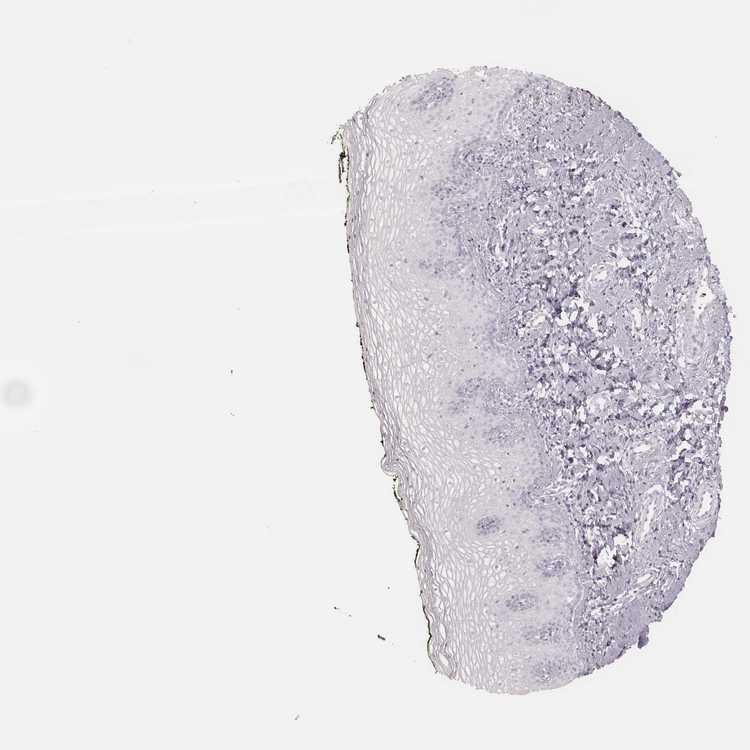

VAGINA - Antibody stainingi

Antibody staining in the annotated cell types in the current human tissue is reported as not detected, low, medium, or high, based on conventional immunohistochemistry profiling in selected tissues. This score is based on the combination of the staining intensity and fraction of stained cells.

Each image is clickable and will lead to virtual microscopy that enables deeper exploration of all samples and also displays staining intensity scores, fraction scores and subcellular localization as well as patient and tissue information for each sample.

Antibody HPA065523

Squamous epithelial cells Not detected